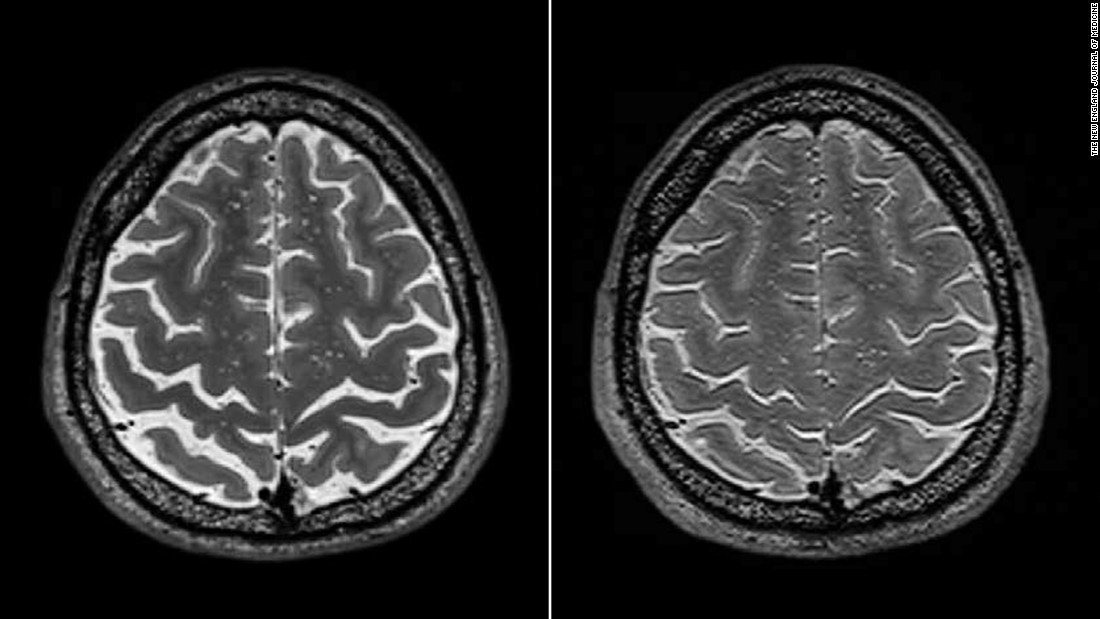

▼長期滞在した宇宙飛行士の脳(左)、右は滞在前に撮影したもの

そのうち頭頂葉と前頭葉の境界にあたる『中心溝』と呼ばれる溝の幅が狭くなっていたのは短期滞在者は3人、長期滞在者は17人。頭頂部の脳脊髄液空間が狭くなっているのは短期滞在者が1人、長期滞在者は12人となりました。また長期滞在者のうち3人に関しては視覚障害頭蓋内圧症候群を発症しており何れも中心溝が狭くなっていたとしています。